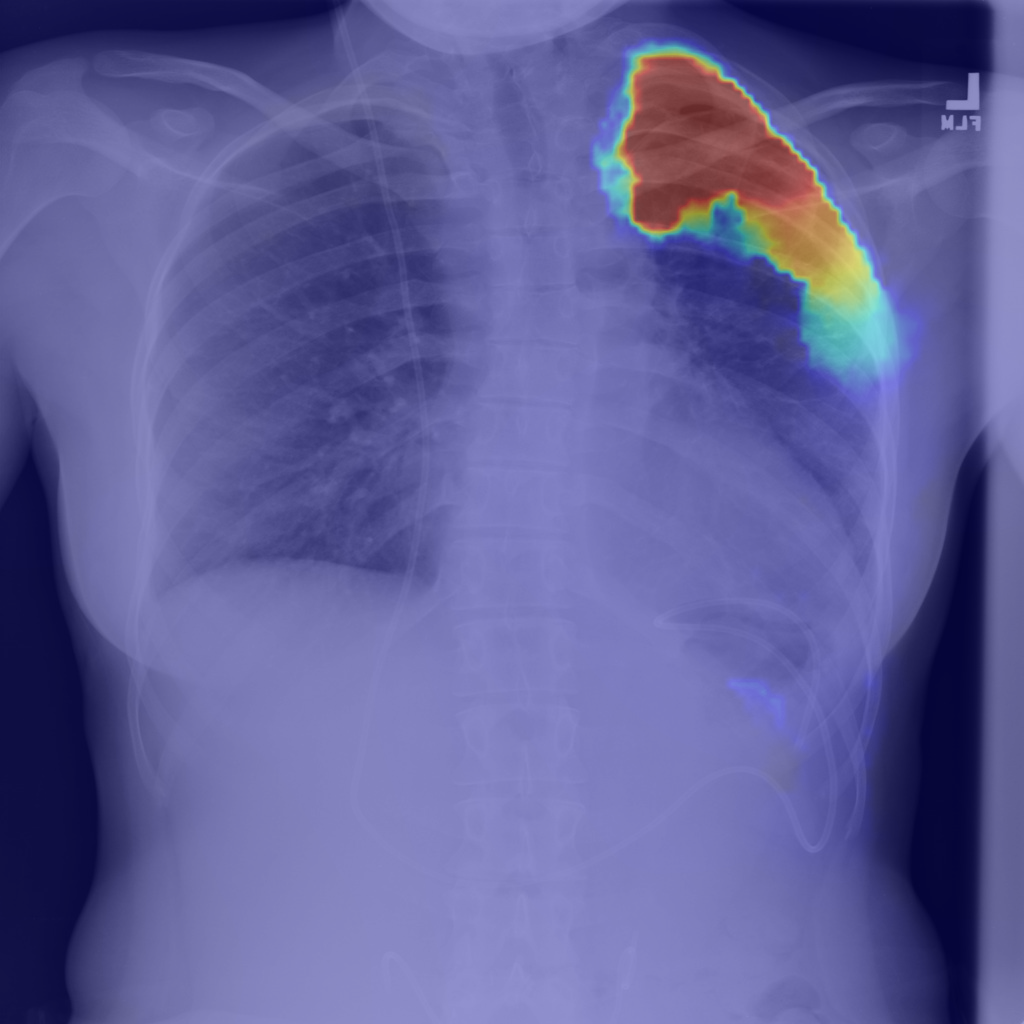

Refer to caption

(b) Step1.CAM

Figure 2: Segmentation predictions for (a) a random image from test set of SIIM-ACR Pneumothorax produced at each step of our approach: (b) CAM extraction, (c) IRNet, (d) U-Net segmentation, compared to (e) ground truth mask.

We present method’s explainability via disease localization regions; cf. Figure 1. We provide qualitative results of segmentation on validation images from both datasets in Figure 2 and Figure 3. We show the resulting maps at each step of our method; the figures demonstrate how the performance improves after each step. We achieve comparable results to state-of-the-art method on PASCAL VOC 2012; cf. Table 4.